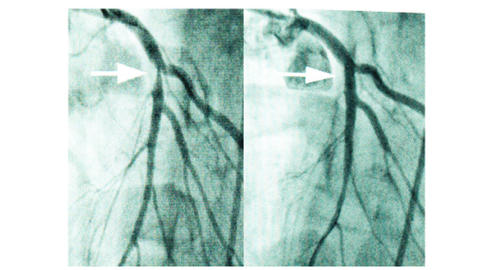

Hier kommt die zweite Stärke der Methode zum Tragen. Entdecken Ärztinnen und Ärzte in den Herzkranzgefäßen eine bedeutsame Engstelle (Stenose) oder behandeln sie Patientinnen und Patienten im akuten Herzinfarkt, versuchen sie, Koronararterien wieder durchgängig zu machen. Die Technik heißt perkutane transluminale koronare Angioplastie (PTCA) oder percutaneous coronary intervention (PCI). Was ist darunter zu verstehen? Über den Katheter lassen sich nicht nur Engstellen der Herzkranzgefäße bildlich darstellen, sondern auch öffnen. Dazu schiebt man in vielen Fällen zunächst einen Druckdraht in das verengte Kranzgefäß, der ggf. eine noch präzisere Bestimmung der Engstelle ermöglicht (Druckdrahtmessung; FFR, IFR, RFR). Im Falle einer nachgewiesen bedeutsamen Stenose kann über den Draht ein Ballon bis an die Engstelle vorgebracht und mit hohem Druck entfaltet werden. So wird die Verengung erweitert und ein verbesserter Blutfluss erzeugt. Hier macht man sich die Elastizität der Gefäße zu Nutze: Ablagerungen werden vom Ballon in die Gefäßwand gedrückt. Um in diesem Bereich eine erneute Verengung zu verhindern, setzen Ärztinnen und Ärzte während derselben Untersuchung kleine metallnetzartige Gefäßstützen in das Blutgefäß ein. Diese sogenannten „Stents“ sind heute ganz überwiegend beschichtet und setzen Medikamente frei, damit der behandelte Bereich nicht wieder zuwächst. Gefäßstützen, die vom Körper nach einiger Zeit abgebaut werden, haben bis heute keine überzeugenden Langzeitergebnisse gezeigt. Welche Stents sich eignen und welche gerinnungshemmenden Arzneistoffe (sogenannte Plättchenhemmer) anschließend wie lange erforderlich sind, entscheidet die Ärztin oder der Arzt. Grundsätzlich erfolgt eine PTCA als geplanter Eingriff bei der chronisch stabilen koronaren Herzkrankheit, aber auch als lebensrettender Notfalleingriff beim akuten Herzinfarkt.